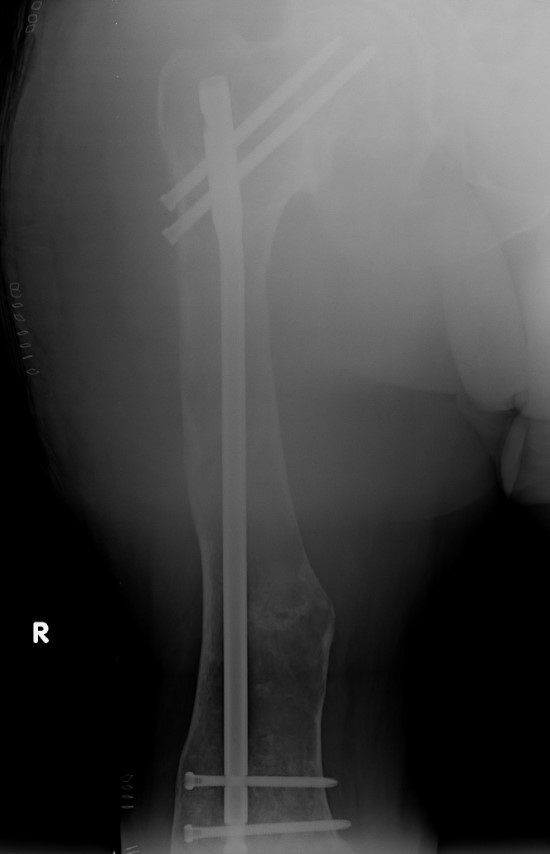

Corrective osteotomy / Intra-medullary nailing

Mainstay of treatment

Ippolito et al J Orthop Traumatol 2023

- 24 patients with 34 femurs and 14 tibias requiring intra-medullary nailing

- mean age 32

- osteotomy and deformity correction often required

- nonunion / delayed union / implant failure in 5 cases

Proximal femur coxa vara and shepherds crook deformity

- 11 cases

- initial osteotomy correction of coxa vara and fixation with hip plate

- later osteotomy and correction of shepherds crook / femoral bowing and insertion reconstruction nail

- improved pain and gait

- significant blood loss at both stages